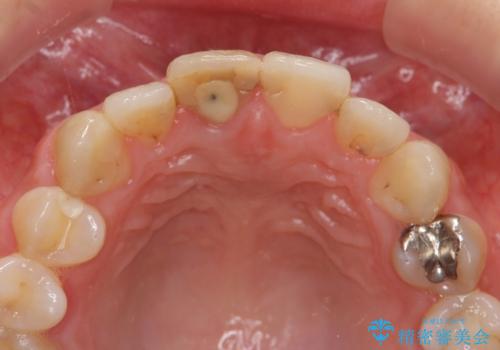

- 「 以前神経を取った歯の変色が気になる。前歯をきれいにして欲しい。」と治療を希望され来院されました。

目立つ上顎前歯に変色・大きな虫歯治療痕が見られ、審美障害を引き起こしています。

虫歯の徹底的な除去、根管治療を行いセラミック治療に入る前の環境をしっかりと整えたのち審美的なジルコニアセラミックで治療を仕上げました。